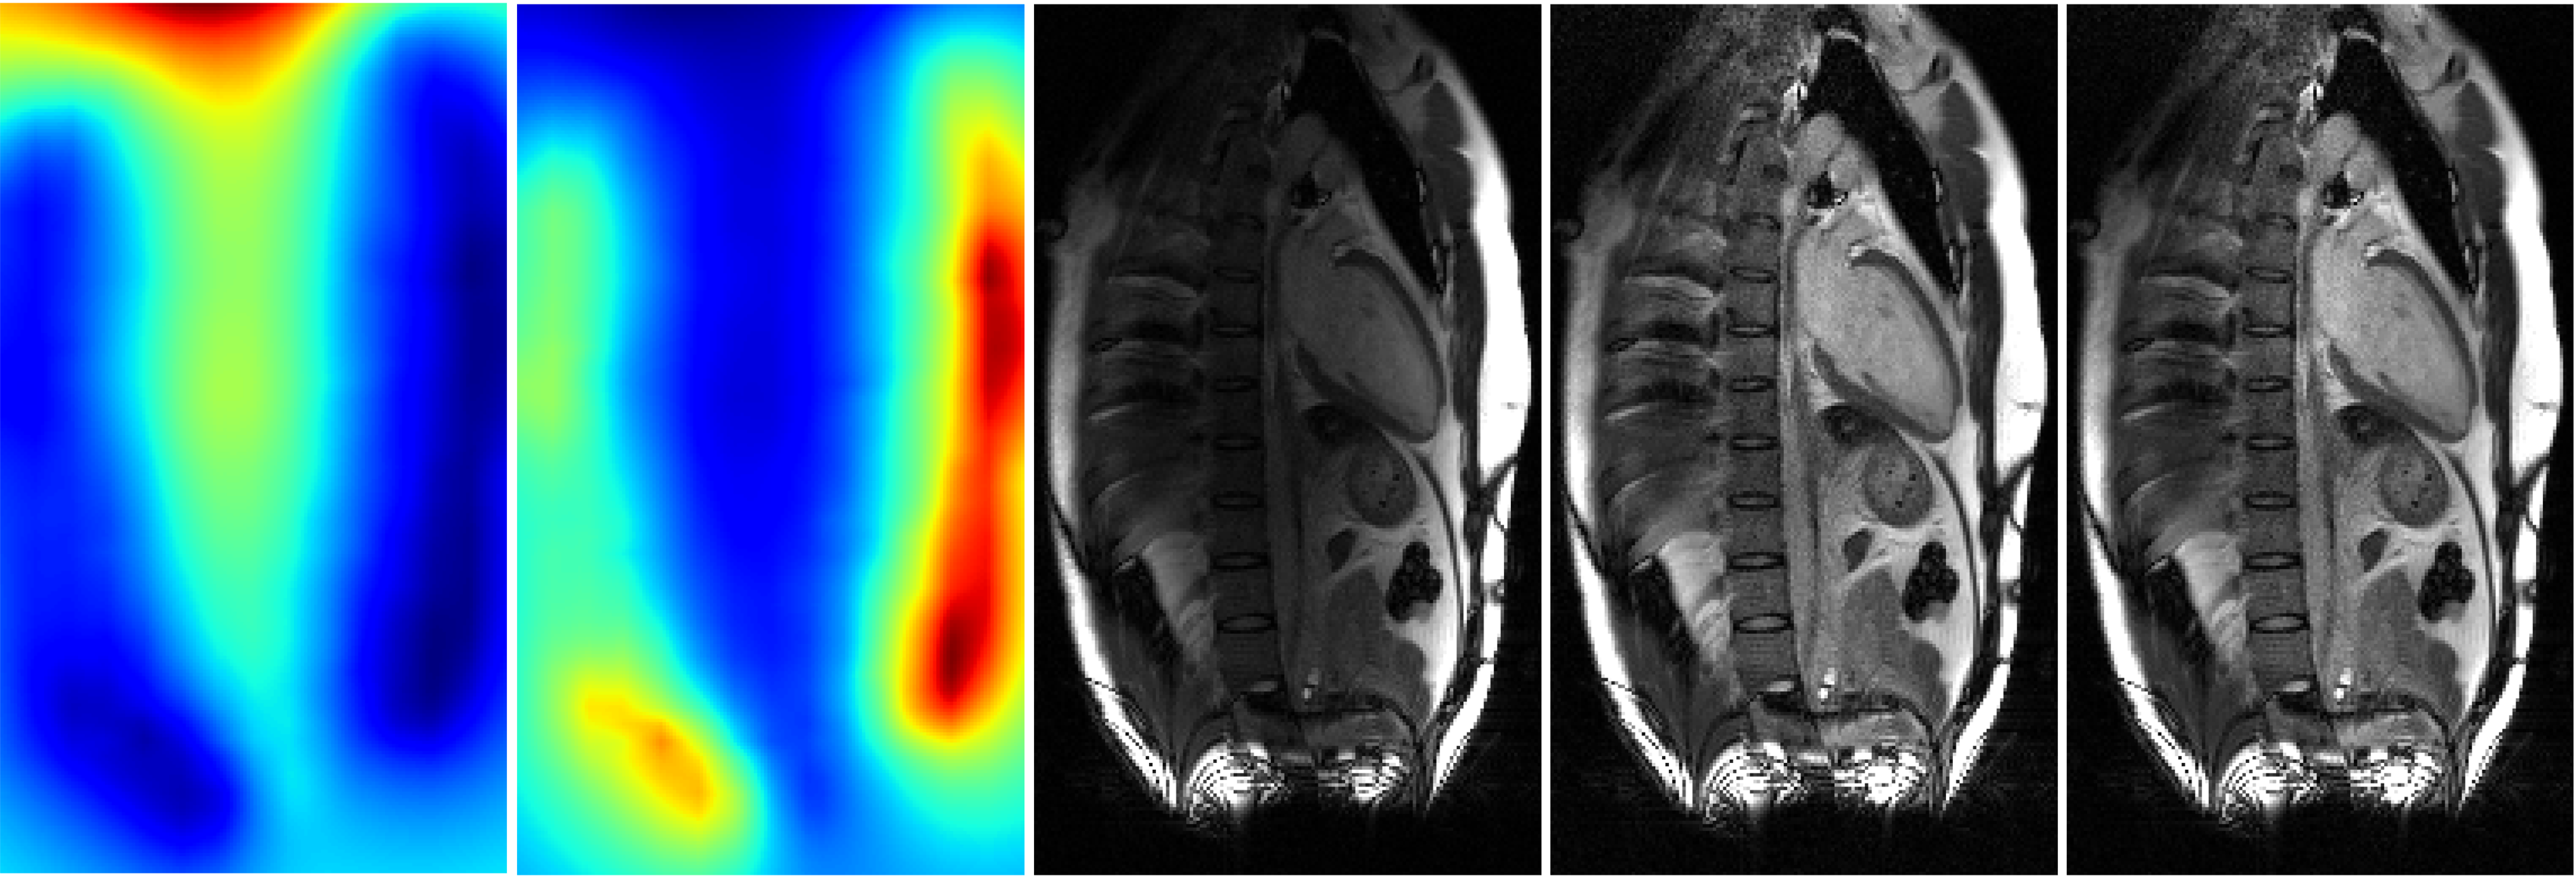

3.2 Cardiac MRI study

For measured MRI data, single-shot free-breathing T1-weighted images were collected from a healthy volunteer on a 3T scanner (MAGNETOM Vida, Siemens Healthcare, Erlangen, Germany) running on an XA31A platform. The data were collected without contrast using phase-sensitive inversion recovery sequence [6] and were prospectively undersampled at the acceleration rate of two. The raw data file, containing the pre-scan as well as the k-space measurements , was copied from the scanner for offline processing in Python. Representative results are shown in Fig. 4. Both and offer improvement over the uncorrected image .

The quality of SCC correction depends on the spatial homogeneity of . Due to the much larger size of the body coils, one expects to be more uniform than . In practice, however, may not offer the perfect uniformity, leading to residual intensity variation in and . The results presented in Fig. 3 and Fig. 4 show little difference between and . These reconstructions are based on SENSE without regularization. However, for deep learning-based methods or methods that use regularization, e.g., compressed sensing [7], we expect and to differ. This is because has better spatial uniformity than , which can potentially make more amenable to sparsity-based or generative priors.